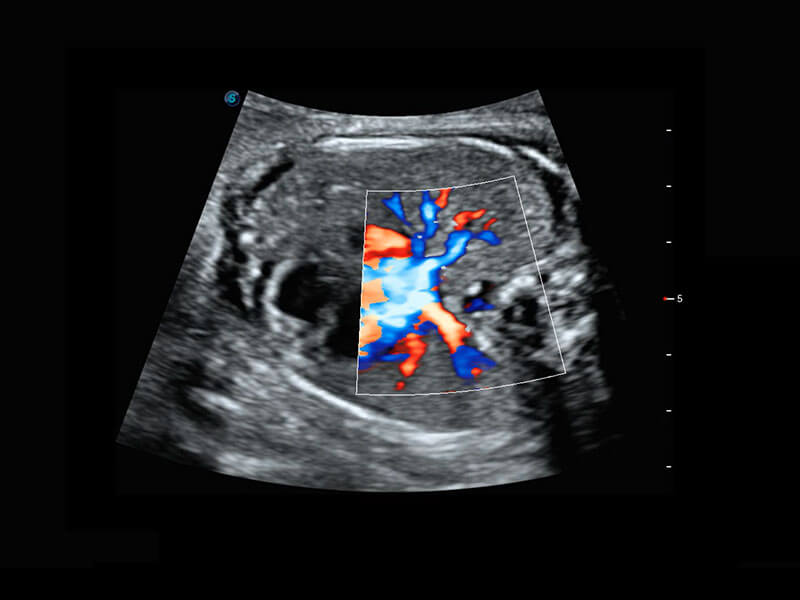

乳腺超声 / 新生儿

P60搭载宽频带线阵探头、宽景成像、弹性成像技术,为您提供乳腺应用方案。P60支持高频相控阵探头、线阵探头、腹部高频探头、腹部微凸探头等,丰富的探头群搭载敏感的彩色血流成像,适用于新生儿多种脏器检测要求,满足新生儿筛查需求。

• 新生儿肝血管癌